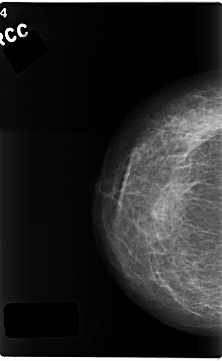

C_0216_1.RIGHT_CC

RIGHT_CC LINES 4688 PIXELS_PER_LINE 2880 BITS_PER_PIXEL 12 RESOLUTION 50 NON_OVERLAY